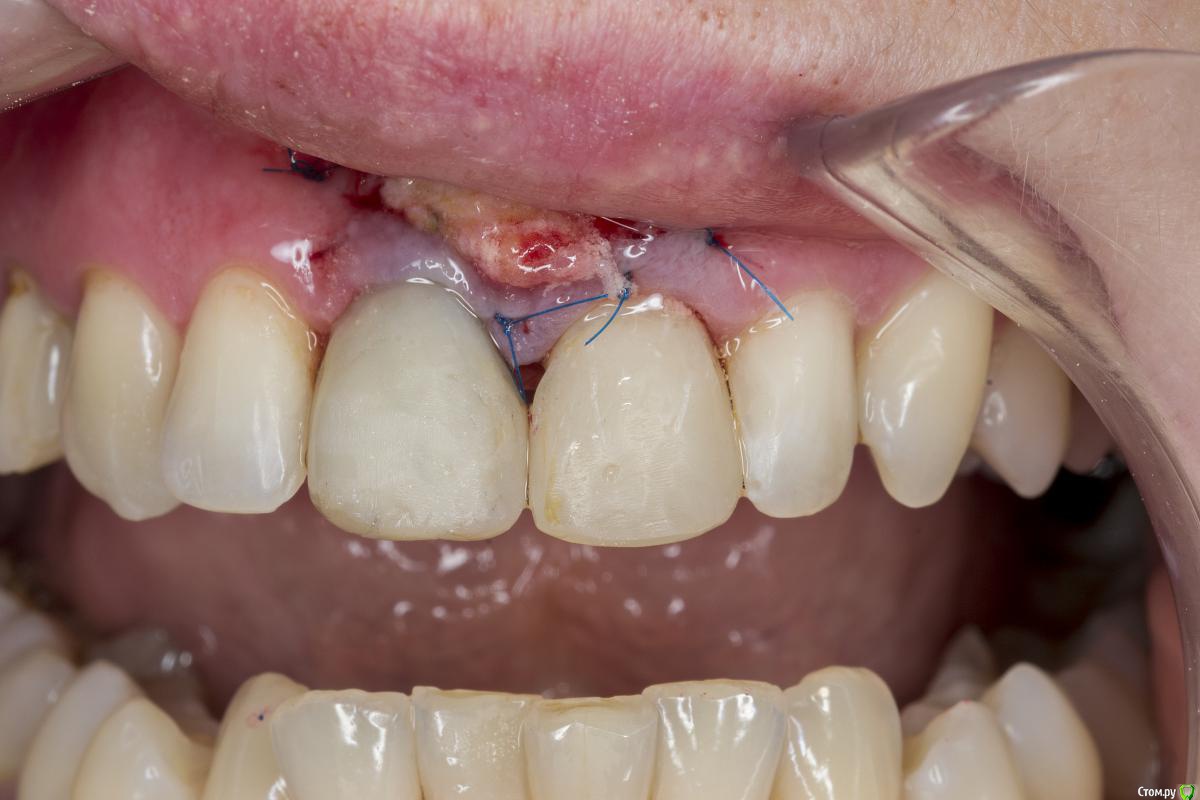

Александр07 Опубликовано 26 июня, 2020 Автор Поделиться Опубликовано 26 июня, 2020 Коллеги, скидываю фото проделанной работы, прошло около 1.5 мес, есть результат, спасибо за помощь, если какие то замечания /советы есть пишите 4 Ссылка на комментарий

колесников Опубликовано 26 июня, 2020 Поделиться Опубликовано 26 июня, 2020 (изменено) Здравствуйте! Не видел этого поста раньше,бегло посмотрел. Определенно проблема была в выборе высоты абатмент и объёме реставрации. Вы убрали композит максимально в основании-это хорошо,но абатмент оставили прежний. Следовало взять новый с высотой уступа 4-5 мм. Край коронки пришеечный следует опустить ниже,иначе десна опять отскочит. И переход слелайте на плавный а под углом,так называемый балкон. Потом будет что отдавить. По Масана сосочек сделали это хорошо и правильно,но с такой реставрацией опасно,мало место лоскуту. К счастью кажется все живы. На данном этапе рекомендую пропилить балкон и этим ограничится. Изменено 26 июня, 2020 пользователем колесников Ссылка на комментарий

Александр07 Опубликовано 27 июня, 2020 Автор Поделиться Опубликовано 27 июня, 2020 Справились одним трансплантом в итоге?)Два, один под сосочек с бугра второй вестибулярно с неба Сст 1 Ссылка на комментарий

Александр07 Опубликовано 27 июня, 2020 Автор Поделиться Опубликовано 27 июня, 2020 Здравствуйте! Не видел этого поста раньше,бегло посмотрел. Определенно проблема была в выборе высоты абатмент и объёме реставрации. Вы убрали композит максимально в основании-это хорошо,но абатмент оставили прежний. Следовало взять новый с высотой уступа 4-5 мм. Край коронки пришеечный следует опустить ниже,иначе десна опять отскочит. И переход слелайте на плавный а под углом,так называемый балкон. Потом будет что отдавить. По Масана сосочек сделали это хорошо и правильно,но с такой реставрацией опасно,мало место лоскуту. К счастью кажется все живы. На данном этапе рекомендую пропилить балкон и этим ограничится.С высотой да, выше надо было , на постоянной учтём , по балкону принцип понятен, - больше места для транса, но все же времянки рекомендуют плавными делать, без резких переходов, поэтому такой вопрос если выпиливать максимально места для тр-та то когда переводить временную коронку на плавный дизайн , через месяц где-то когда транс приживется и стабилизируется первично ? Ссылка на комментарий

колесников Опубликовано 27 июня, 2020 Поделиться Опубликовано 27 июня, 2020 Через 2 недели. Но можно и месяц Ссылка на комментарий